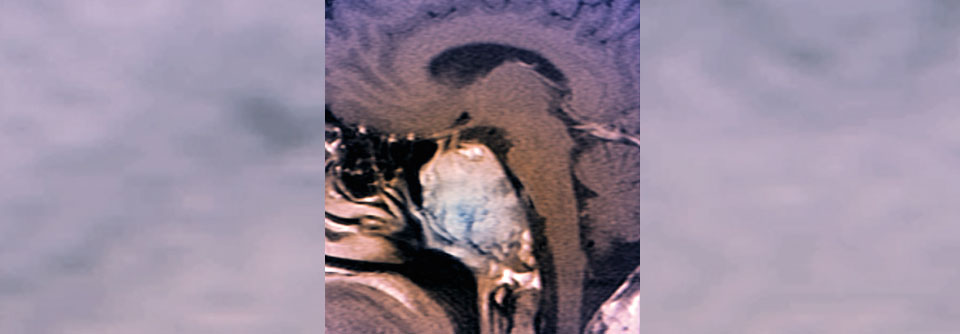

Die pHLH ist selten und potenziell lebensbedrohlich. Die pHLH ist selten und potenziell lebensbedrohlich. © wikimedia/Nephron (CC BY-SA 3.0)

Die primäre hämophagozytische Lymphohistiozytose (pHLH) ist ein seltenes und potenziell lebensbedrohliches hyperinflammatorisches Syndrom, dem eine Dysregulation der Immunantwort zugrunde liegt und das oft mit genetischen Defekten der zytotoxischen Funktion assoziiert ist. „Die geschätzte Inzidenz liegt bei einem Fall pro 50 000 Neugeborenen“, informierte Professor Dr. Franco Locatelli vom Ospedale Pediatrico Bambino Gesù in Rom. Ähnlich wie bei der Sepsis entwickelt sich ein Zytokinsturm mit Freisetzung proinflammatorischer Zytokine. Klinisch manifestiert sich die pHLH mit: